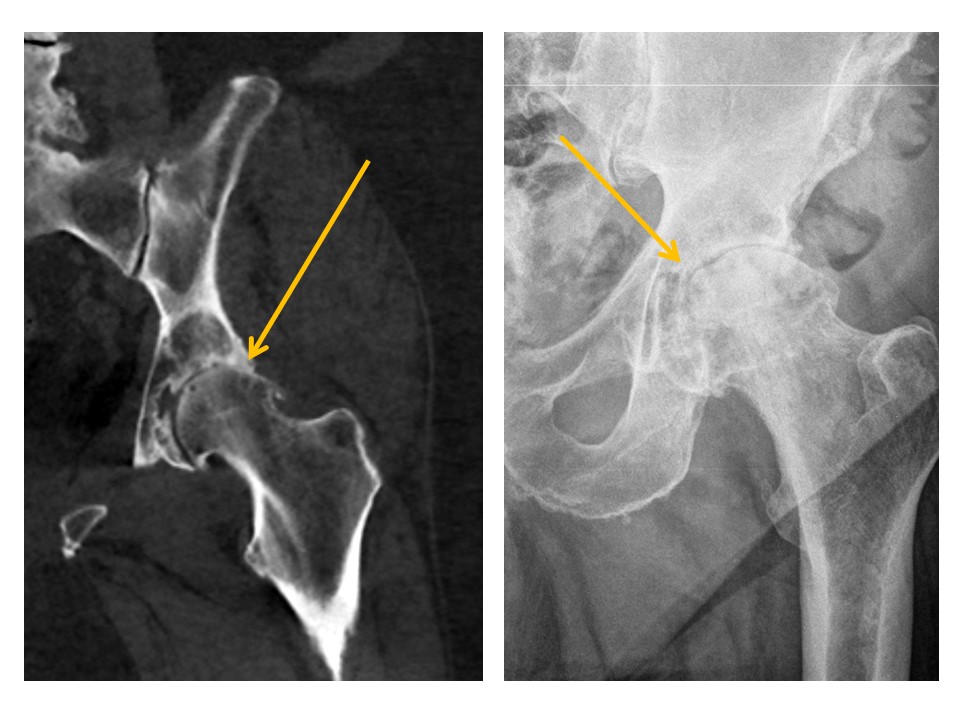

HIPS/PROXIMAL FEMURS

Ilioischial lines are disrupted. [Yes/No]

Iliopubic (iliopectineal) lines are disrupted. [Yes/No]

Anterior walls of the acetabula are disrupted. [Yes/No]

Posterior walls of the acetabula are disrupted. [Yes/No]

Anterior walls of the acetabula are lateral to the posterior walls (“crossover sign”). [Yes/No]

Acetabular roofs are discontinuous. [Yes/No]

The teardrop distance is asymmetric. [Yes/No]

There are radiographic findings of hip osteoarthritis or inflammation. [Yes/No]

The cortices of the femoral heads are irregular. [Yes/No]

There is abnormal osseous density of the femoral heads. [Yes/No]

The center edge angle of the femoral heads is abnormal. [Yes/No]

There is osseous prominence at the lateral femoral head/neck junctions. [Yes/No]

There are fractures of the femoral neck, intertrochanteric region, or subtrochanteric region. [Yes/No]